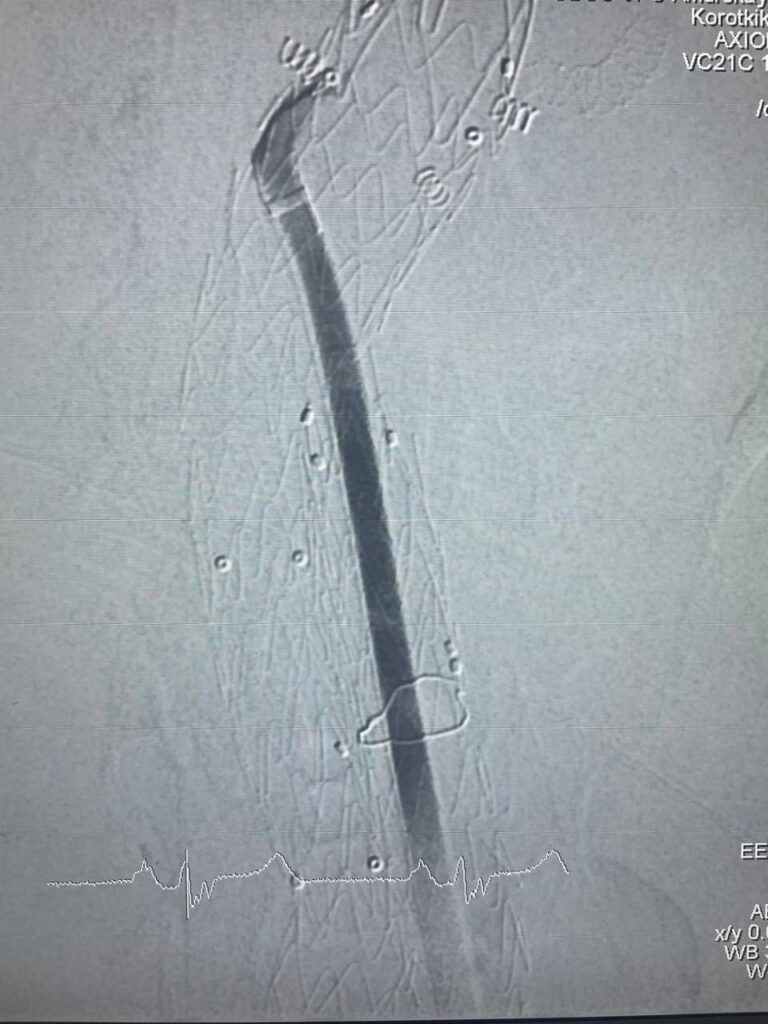

В клинике кардиохирургии Амурской медакадемии провели операцию по

эндопротезированию брюшного отдела аорты и подвздошных артерий с

эндофиксацией пациенту с аневризмой аорты. Это делается для того,чтобы

сам эндопротез (графт) не сместился вверх или вниз,тем самым снижаются

риски осложнений.

Операцию выполнил главный врач клиники Александр Владимирович Коротких совместно с Маратом Равилевичем Шарафутдиновым, который является ведущим специалистом в России в данном направлении.